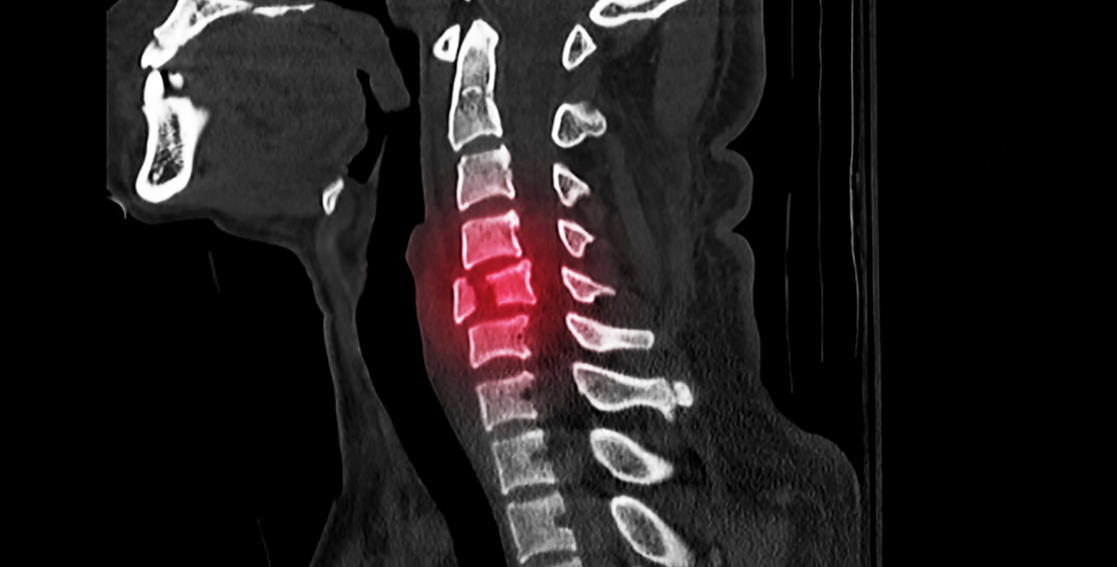

脊髓損傷(SCI)是由于創(chuàng)傷導(dǎo)致的脊髓結(jié)構(gòu)破壞,引起感覺、運動和自主神經(jīng)功能障礙。該病每10萬人年發(fā)病率達13例,可導(dǎo)致部分或完全性癱瘓,嚴重影響患者生活質(zhì)量并給社會帶來了巨大經(jīng)濟負擔。

脊髓損傷